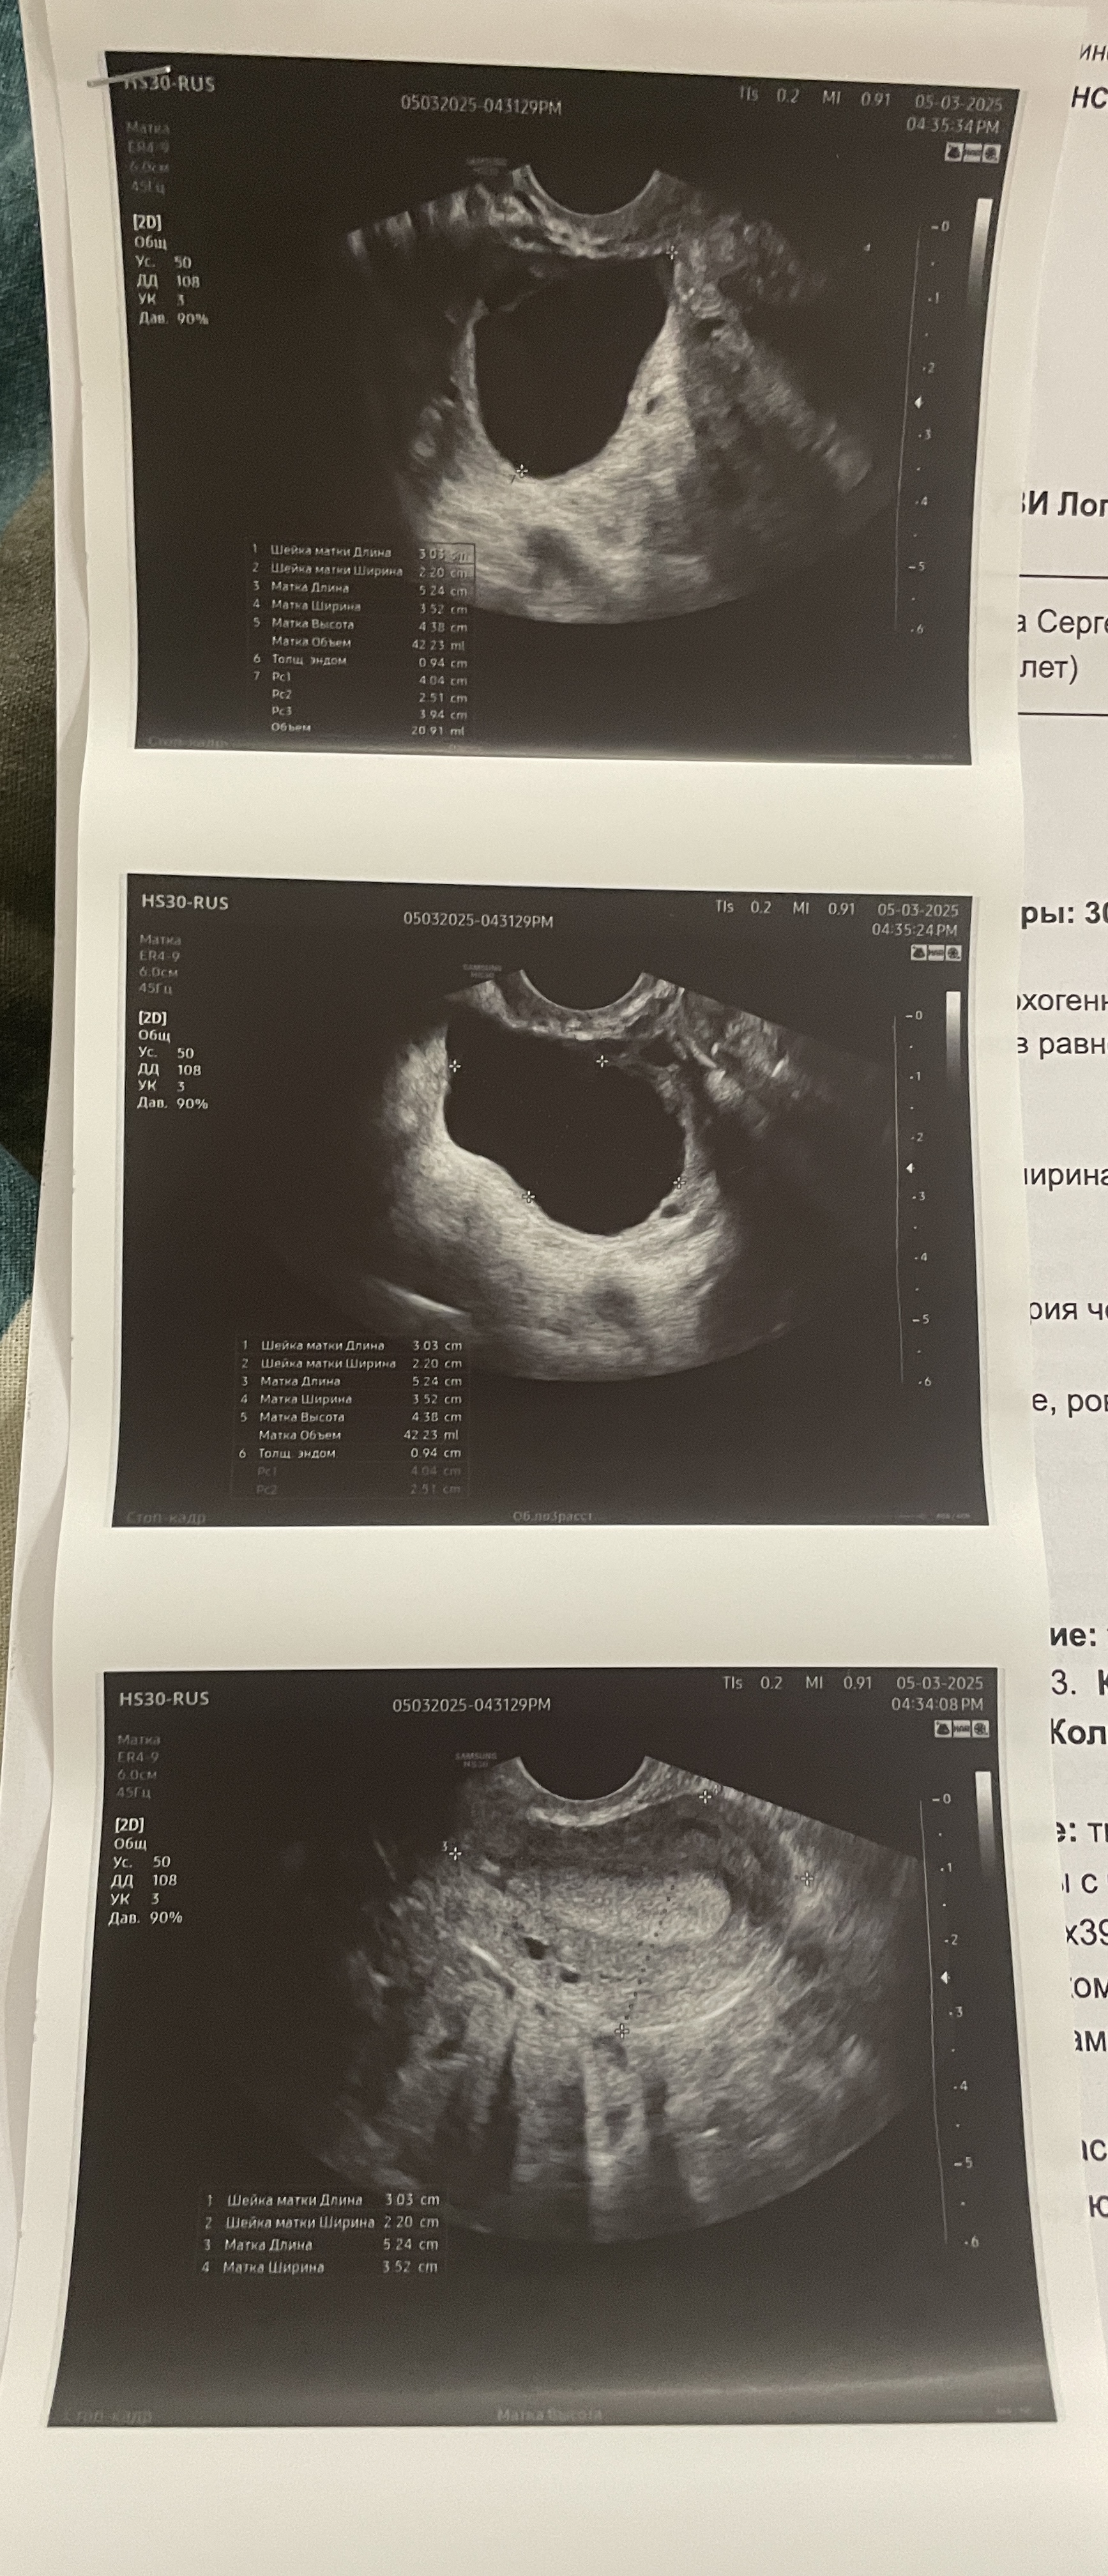

Затянул бок, пошла на узи. Итог. Опасна ли двухкамерная киста? Стоит ли бить тревогу? Есть МФЯ. Возможна ли двойная овуляция из одного яичника? 40 мм в длину, по центру перегородка. Если это два фолликула, то каждый по 20 мм. Такие вот рассуждения